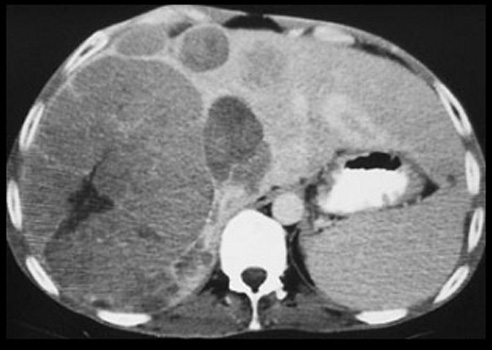

Liver metastasis is a common condition presenting as liver mass.

Liver metastasis

Multiple hypo dense lesions seen in the liver with no significant contrast enhancement.

Primary: Colon carcinoma